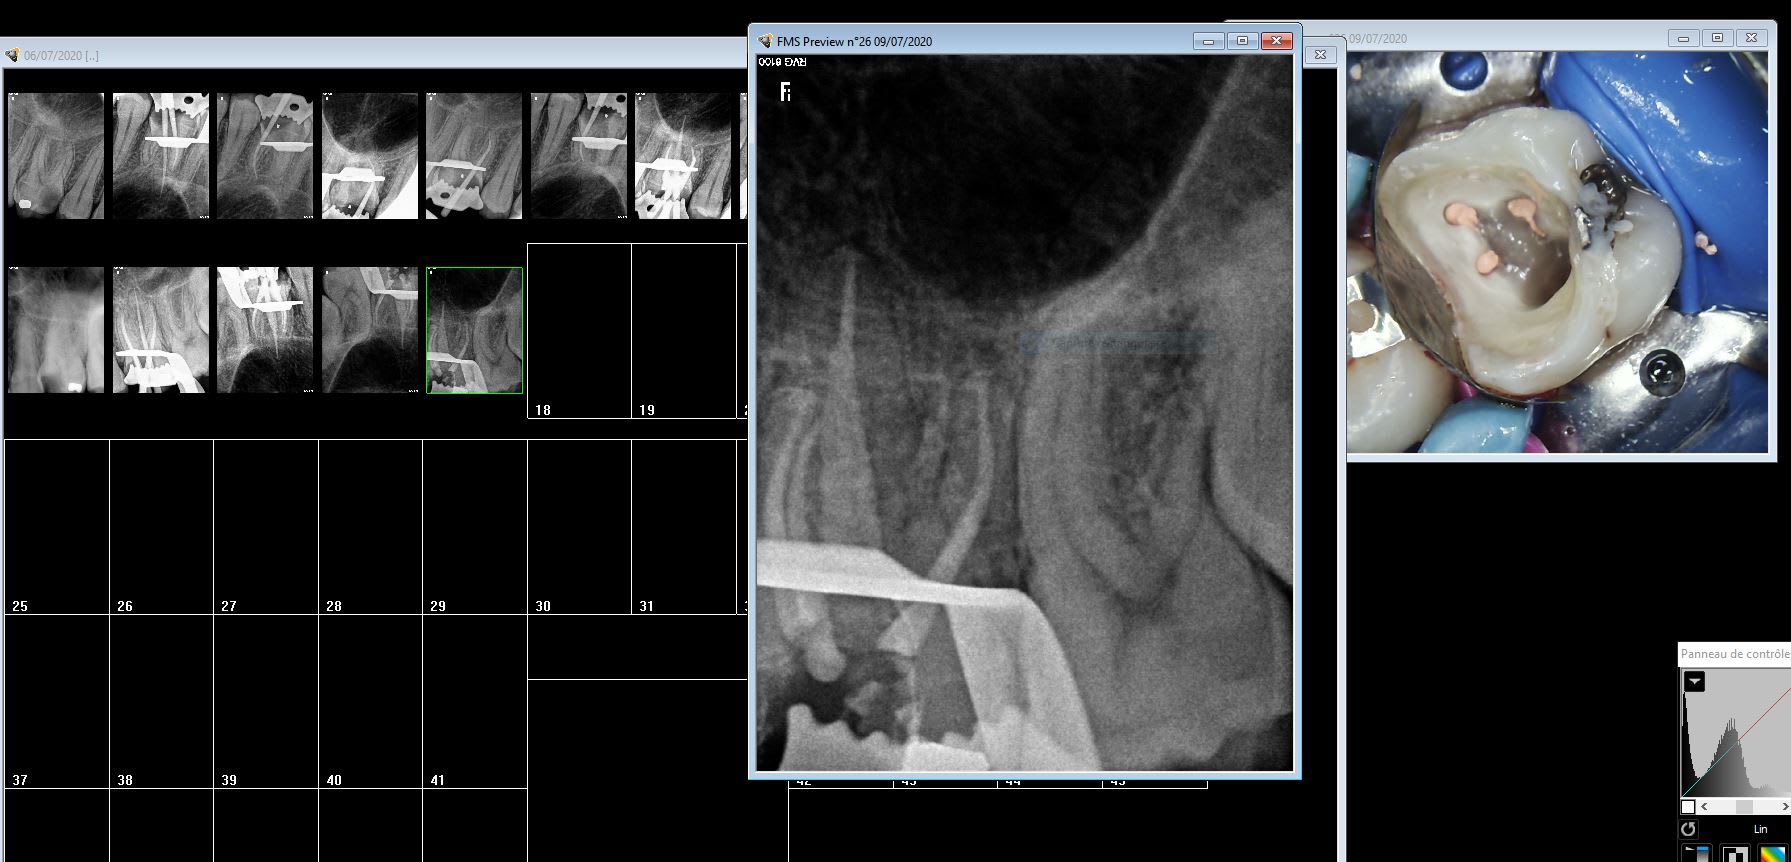

bifide.

Deux canaux fusionnés avec séparation avant l'apex comme le montre la radio. C'est aux protapers golds sans instrumentation manuelle.

Tiens tu le crois ça ? Une 26 bifide. Du jamais vu.

Eh eh!!!! 12 radios contrôles..........toi t'as plus confiance dans tes localisateurs ;-))))